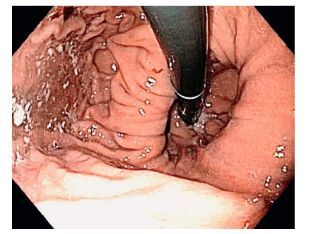

Trong quá trình nội soi tiêu hóa, khi đưa quan sát các phần của dạ dày ở tư thế máy thẳng, bác sĩ nội soi sẽ quặt ngược dây soi để khảo sát các vùng của đáy vị, tâm vị dạ dày, khi đó, sẽ quan sát được hình ảnh các nếp niêm mạc hội tụ tại chỗ nối thực quản – dạ dày, đó là nếp van thực quản – dạ dày.

Vai trò của nội soi thực quản dạ dày trong đánh giá bất thường nếp van dạ dày – thực quản.

Nội soi thực quản, dạ dày tá tràng - Esophagogastroduodenoscopy (EGD) là phương pháp đánh giá tiêu chuẩn để kiểm tra đường tiêu hóa trên. Khả năng của hàng rào chống trào ngược cơ học có thể được đánh giá nội soi theo hai cách; một cách là đo chiều dài trục của bất kỳ khối thoát vị khe hoành nào hiện diện (giữa khe thoát vị và khớp nối dạ dày thực quản). Do động học sinh lý ở khu vực này, có thể khó đo chiều dài của khối thoát vị khe hoành, ngay cả trong điều kiện lý tưởng. Không rõ độ dài mà thoát vị khe hoành khi nào sẽ trở nên có ý nghĩa lâm sàng, tức là có ý nghĩa bệnh lý, và vì GEJ không cố định, hầu hết các nhà nội soi sử dụng độ dài 2 cm ngưỡng chẩn đoán giữa bình thường và bất thường. Một cách khác để đánh giá GEJ là phân loại nếp van dạ dày thực quản (GEFV) sử dụng phân loại Hill . Các nghiên cứu đã chỉ ra mối liên quan giữa thang điểm Hill và tần suất GERD. Phân độ Hill ở mức cao cũng liên quan đến áp lực cơ vòng thực quản dưới thấp, tăng tần suất thoát vị khe hoành và có khả năng dự đoán đáp ứng kém với điều trị bằng thuốc ức chế bơm proton. Phân loại Hill đã được chứng minh là phù hợp, hữu ích và cung cấp thông tin hữu ích khi đánh giá bệnh nhân nghi ngờ mắc bệnh lý GERD. Viêm thực quản có thể được xác định bằng nội soi và phân loại theo phân loại Los Angeles (LA).